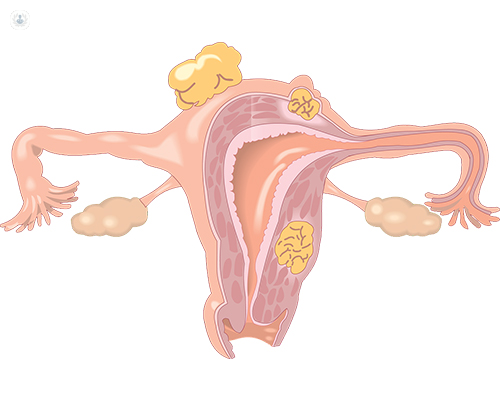

Las mujeres pueden experimentar diversas afecciones a raíz de sus sistema reproductivo. Uno de los más frecuentas son los miomas uterinos.

De acuerdo a la Sociedad Española para el Estudio de los Miomas y la Endometriosis, los miomas uterinos son los tumores benignos más frecuentes entre la población femenina que está en edad reproductiva.

Si bien es una patología no cancerosa en la mayoría de los casos, una cuarta parte de las mujeres que los padece sí puede enfrentar tumores cancerígenos.

¿Qué problemas conllevan los miomas uterinos?

Si bien la mayoría de veces pueden ser benignos, esto no quiere decir que puedan producir ciertas molestias o síntomas. Es más, el 50 y 70% de los miomas son sintomáticos.

De acuerdo a la Sociedad Española mencionada anteriormente, estos miomas sintomáticos "comprometen la fertilidad y limitan la calidad de vida de las pacientes, hasta el punto de, en algunos casos, no poder tener relaciones sexuales plenas debido al dolor".

Igualmente, pueden que produzcan trastornos menstruales, hemorragias, anemia, dolor, síntomas compresivos o aumento del volumen del abdomen.

Si los miomas son muy grandes, también pueden dificultar un embarazo.

Cuando el tamaño del mioma es grande, puede dificultar la implantación del embrión o provocar molestias en la paciente por el espacio que ocupa el mioma en la pelvis.